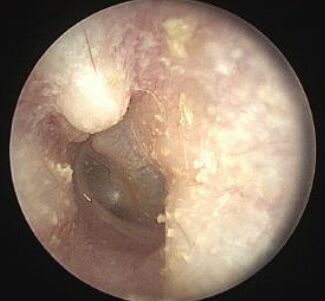

20.一中年男性長年四季晨泳,耳鏡檢查發現如圖,下列何者為最可能之診斷?

Exostoses, sometimes called surfer's ear, are bony overgrowths in the ear canal.

Exostoses are most commonly found in people with a history of cold water exposure.

Multiple smooth, round, bony overgrowths are seen, and often in both ears.

exostosis只要看到骨頭向外長就算歐~

AOE: 會整個耳道變腫不會那樣從中間突起,並且患者沒有耳痛、搔癢、分泌物增加